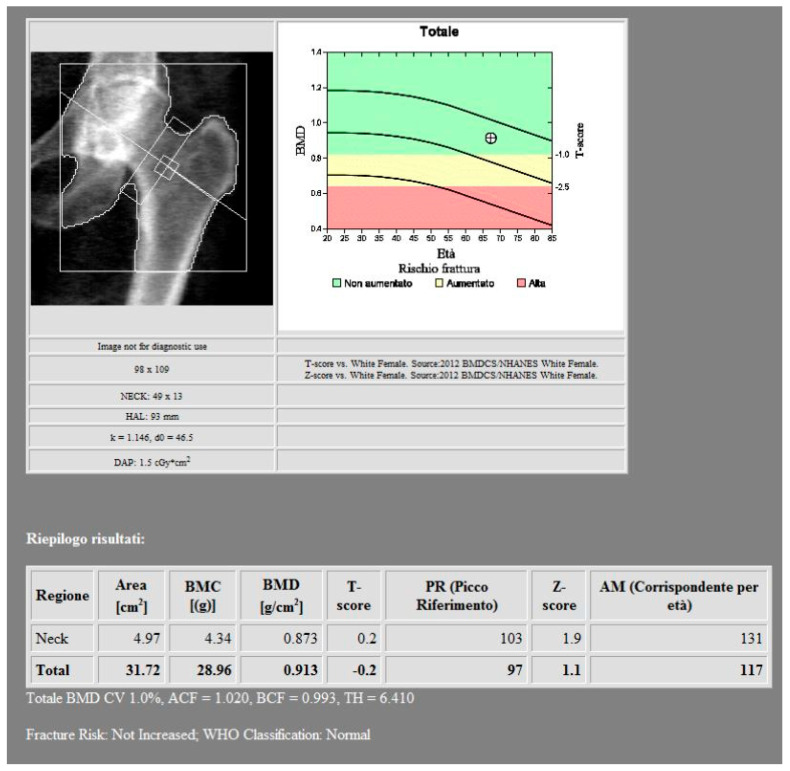

骨矿物质密度(BMD)的评估对骨质疏松症的诊断至关重要。双能x线吸收仪(DXA)是目前的金标准,但它在评估小梁骨方面有局限性,并且容易受到不同的伪影的影响。在这项研究中,我们评估了双能计算机断层扫描(DECT)是否可以作为一种替代方法来评估绝经后接受肿瘤随访的患者的骨密度。本研究对41例6个月内同时行DECT和DXA的患者进行回顾性分析。使用五种不同的基础材料对(BMPs)从DECT中提取骨密度值,并与股骨颈的DXA测量值进行比较。钙-脂肪配对与dxa衍生的骨密度相关性最强(Spearman ρ = 0.797),重复性好(ICC = 0.983)。DXA结果与各种BPM测量之间存在强烈而重要的关联。这些发现支持了当使用特定的BMPs时,DECT在精确和机会性评估BMD变化方面的可能性。这项研究表明,这项技术如何成为传统DXA的有用和有效的替代品,特别是当患者在使用DECT进行肿瘤随访时,最大限度地减少了额外的辐射暴露。

The assessment of bone mineral density (BMD) is essential for osteoporosis diagnosis. Dual-energy X-ray Absorptiometry (DXA) is the current gold standard, but it has limitations in evaluating trabecular bone and is susceptible to different artifacts. In this study we evaluate whether Dual-Energy Computed Tomography (DECT) can be defined as an alternative method for the assessment of BMD in a sample of postmenopausal patients undergoing oncological follow-up. In this study a retrospective analysis was conducted on 41 patients who had both DECT and DXA within six months. BMD values were extracted from DECT using five different base material pairs (BMPs) and compared with DXA measurements at the femoral neck. The calcium-fat pairing showed the strongest correlation with DXA-derived BMD (Spearman's ρ = 0.797) and excellent reproducibility (ICC = 0.983). There was a strong and significant association between the DXA results and the various BPM measurements. These findings support the possibility of DECT in the precise and opportunistic evaluation of BMD changes when employing particular BMPs. This study showed how this technique can be a useful and effective substitute for conventional DXA, particularly when patients are in oncological follow-up using DECT, minimizing additional radiation exposure.